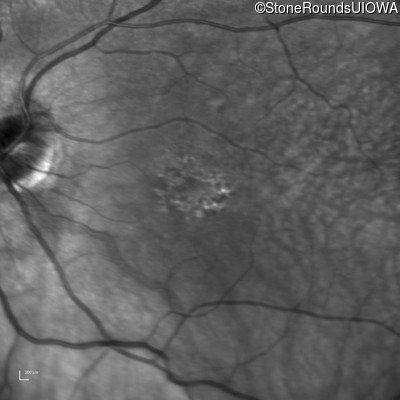

OD OS

This 30 year old man has had reduced acuity and abnormal color vision OU since early childhood.

The clinical features supporting the diagnosis of blue cone monochromacy in this patient include: stable reduced acuity, photophobia and very poor color vision since early childhood, a normal fundus appearance, normally sighted parents and three similarly affected male relatives on the maternal side of his family.

Age at visit: 30 years